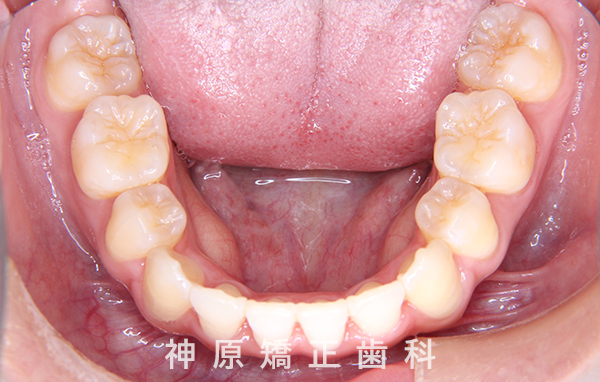

- 治療に用いた主な装置

-

上顎:リンガル(舌側)矯正装置

下顎:唇側矯正装置

歯科矯正用アンカースクリュー - 抜歯 / 非抜歯

- 上下顎左右第一小臼歯の抜歯

治療終了